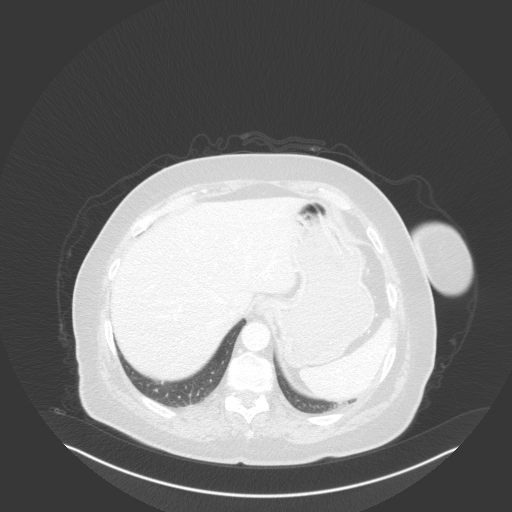

Image Grid

4Γ—3 grid: Rows show different image types (Original NATIVE, Reconstructed NATIVE, Original VENOUS, Generated VENOUS), Columns show windowing techniques (No Window, Lung Window, Mediastinum Window)

Lung window (WL -600, WW 1500 β†’ Low βˆ’1350, High +150)